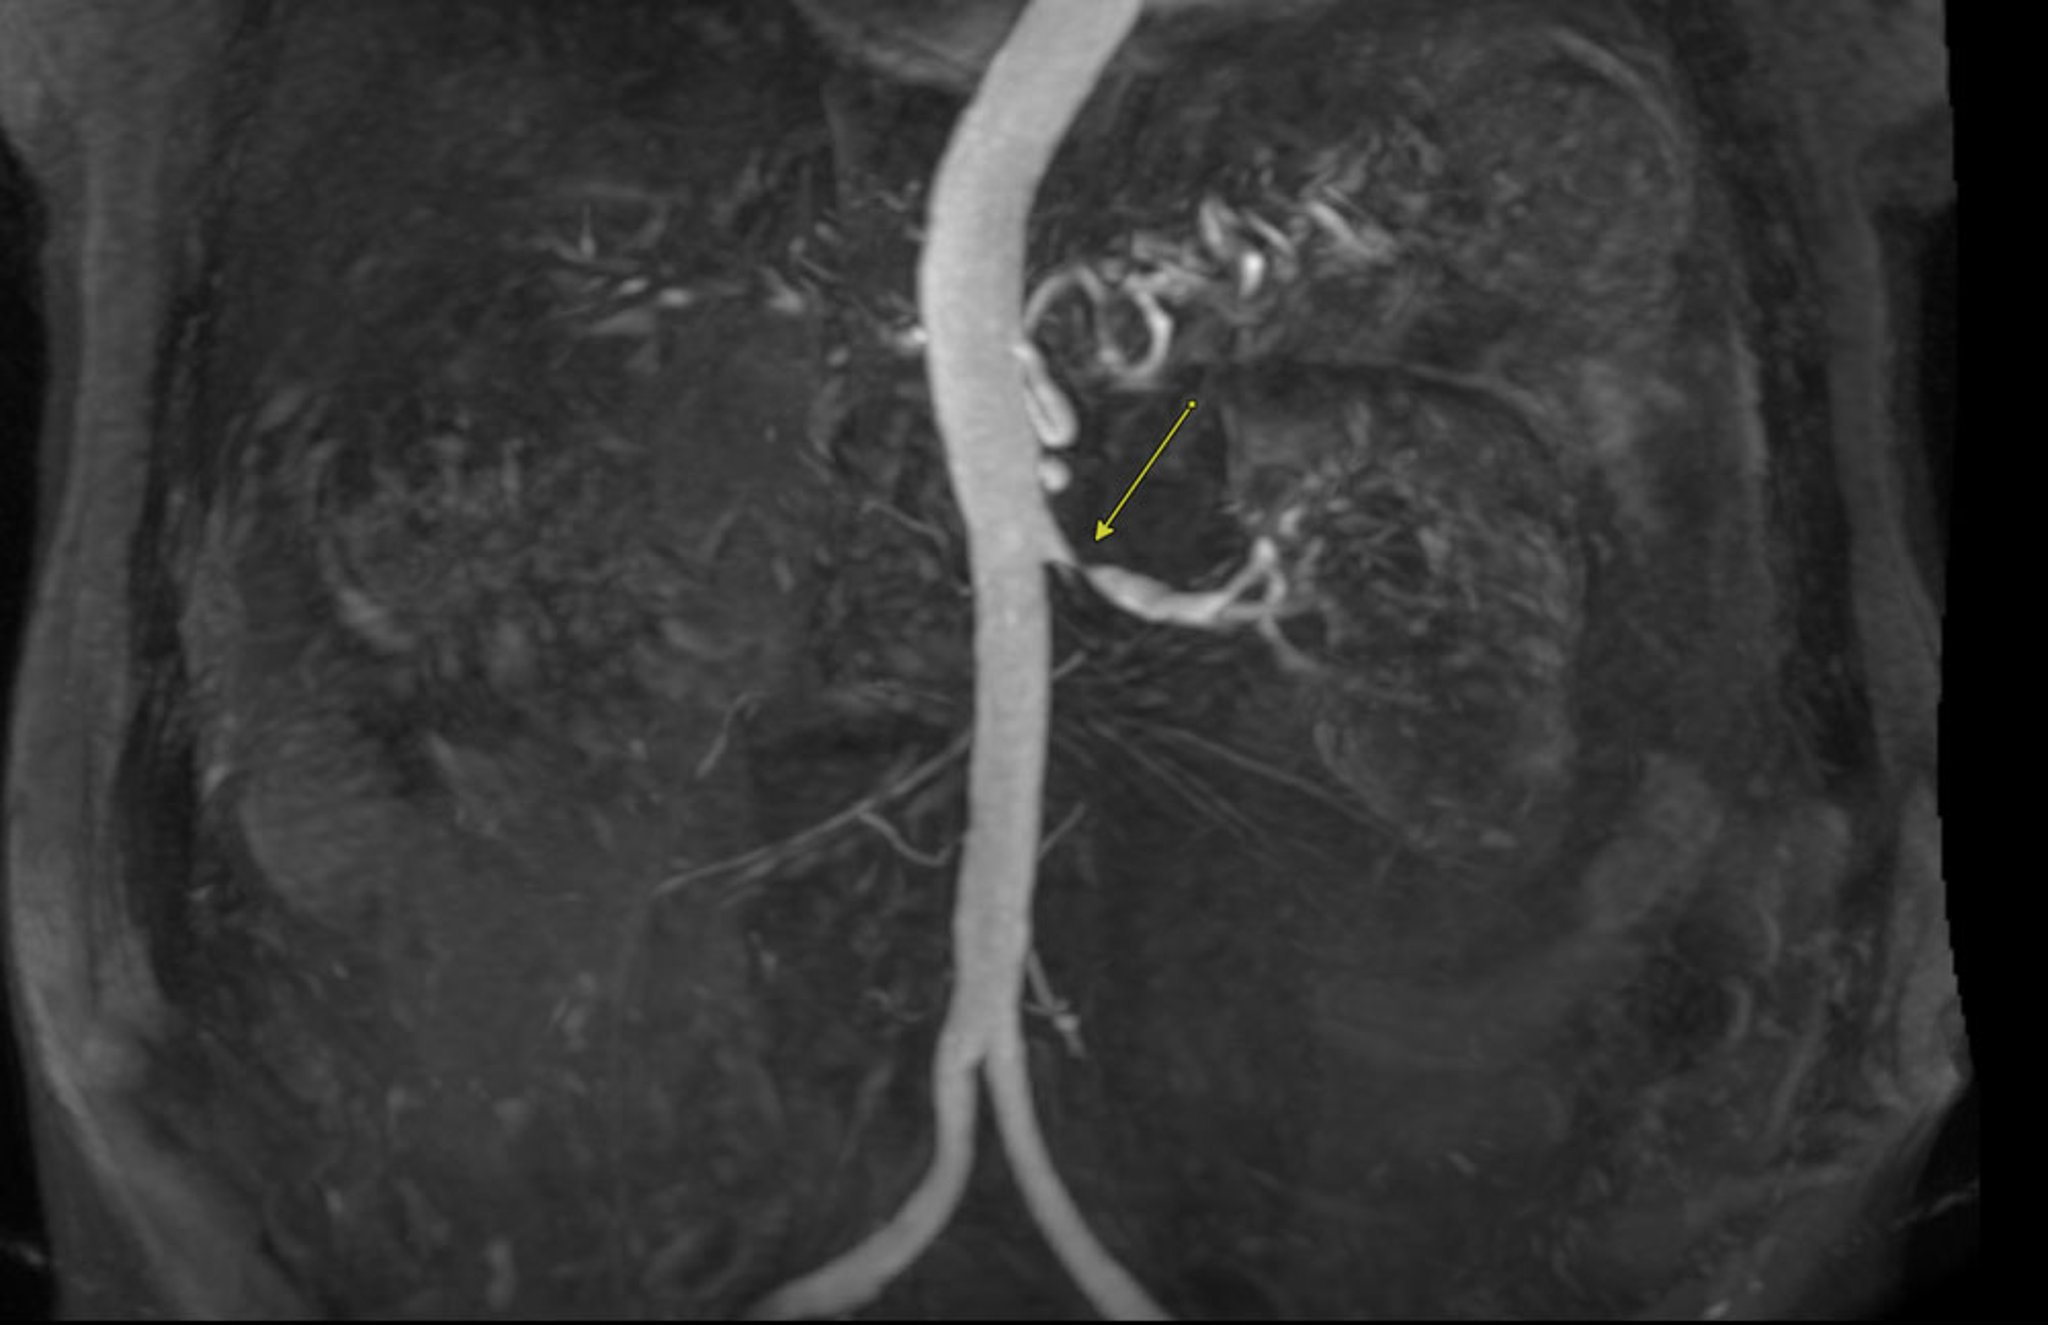

• Angiografia por ressonância magnética (ARM): a ARM pode ser realizada sem contraste ou com contraste à base de gadolínio. É utilizada para avaliar o tamanho vascular e/ou a gravidade da estenose sem expor o paciente à radiação ionizante. Contudo, a resolução espacial dessa técnica é limitada para a visualização de leitos vasculares pequenos e móveis.